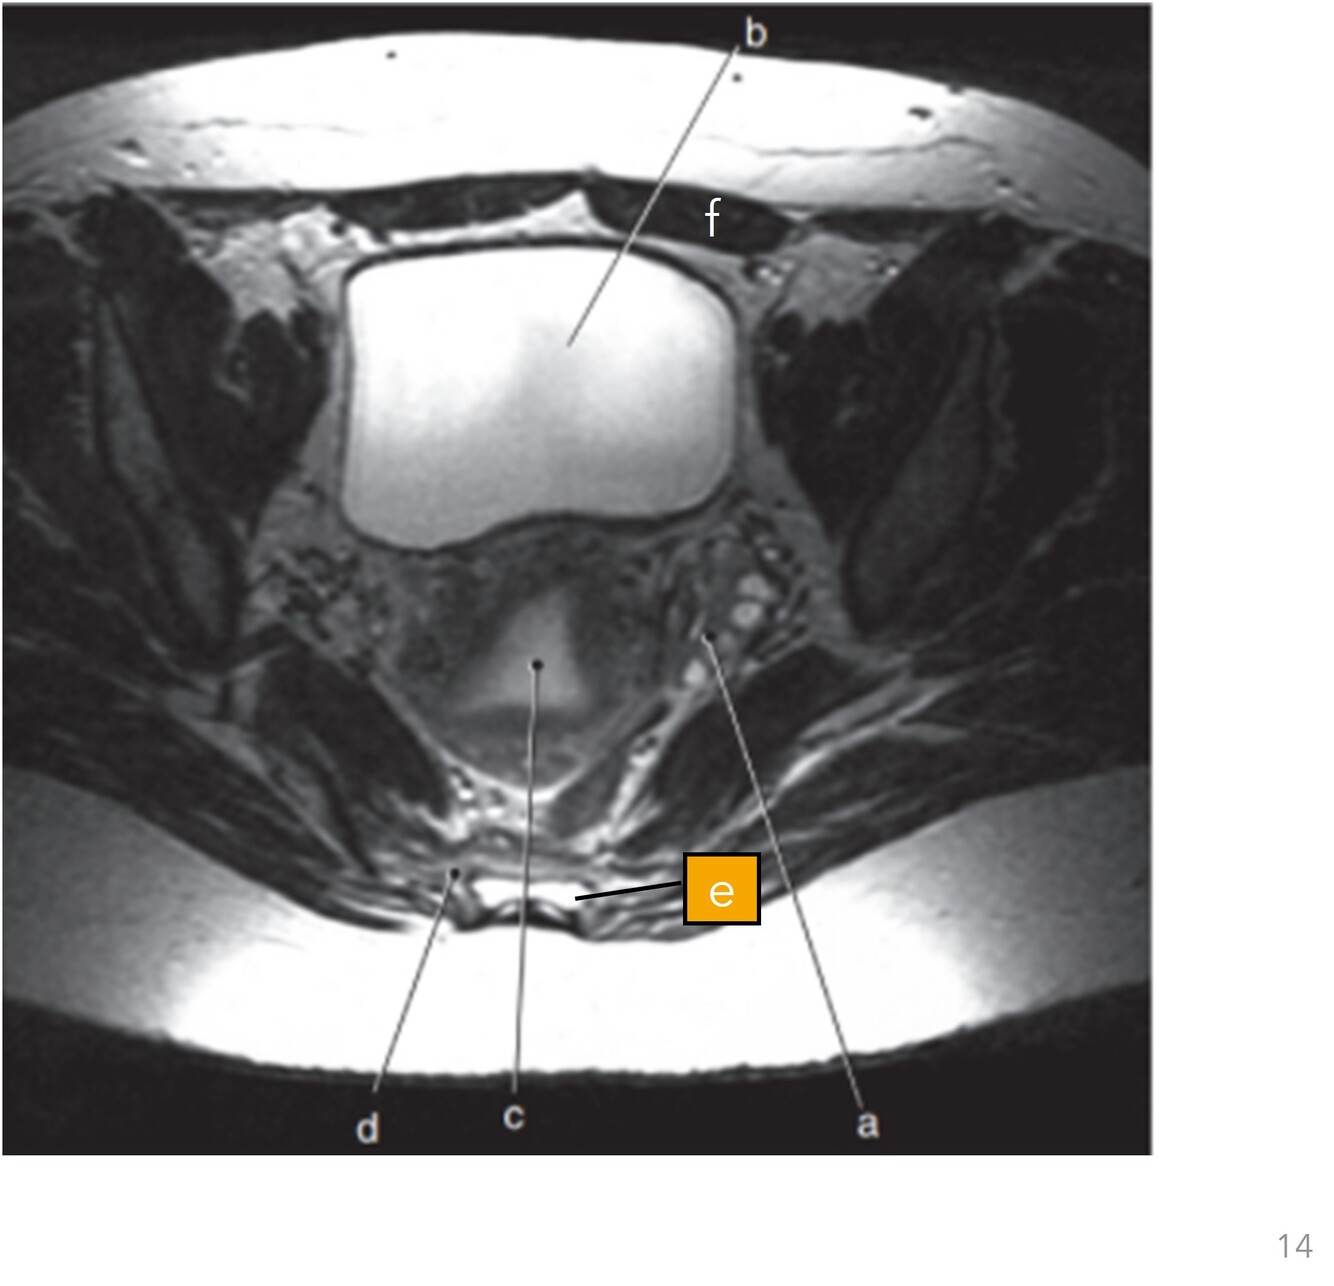

15

Q

Label b,c,e,f

A

b=Bladder

c=Uterine cavity

e=Rectum

f=Left rectus abdominis

How well did you know this?